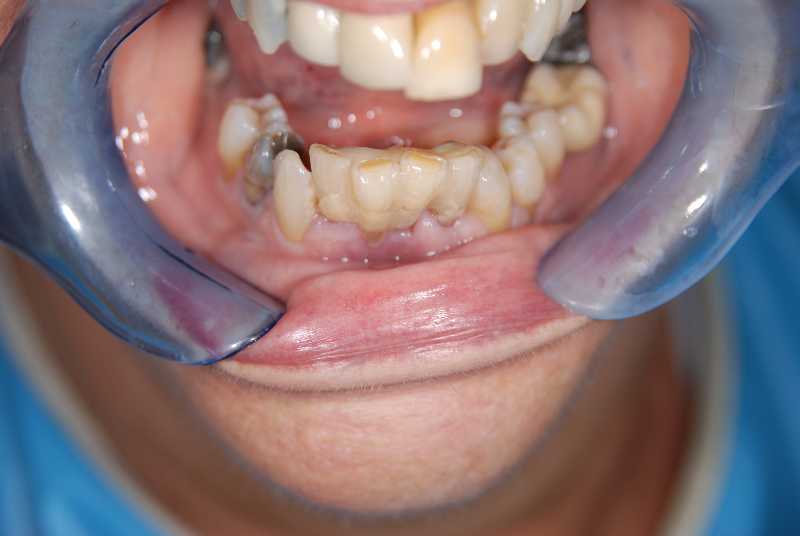

Lower 4-tooth implant bridge (Patient 3)

Intra-oral view (Pre-treatment)